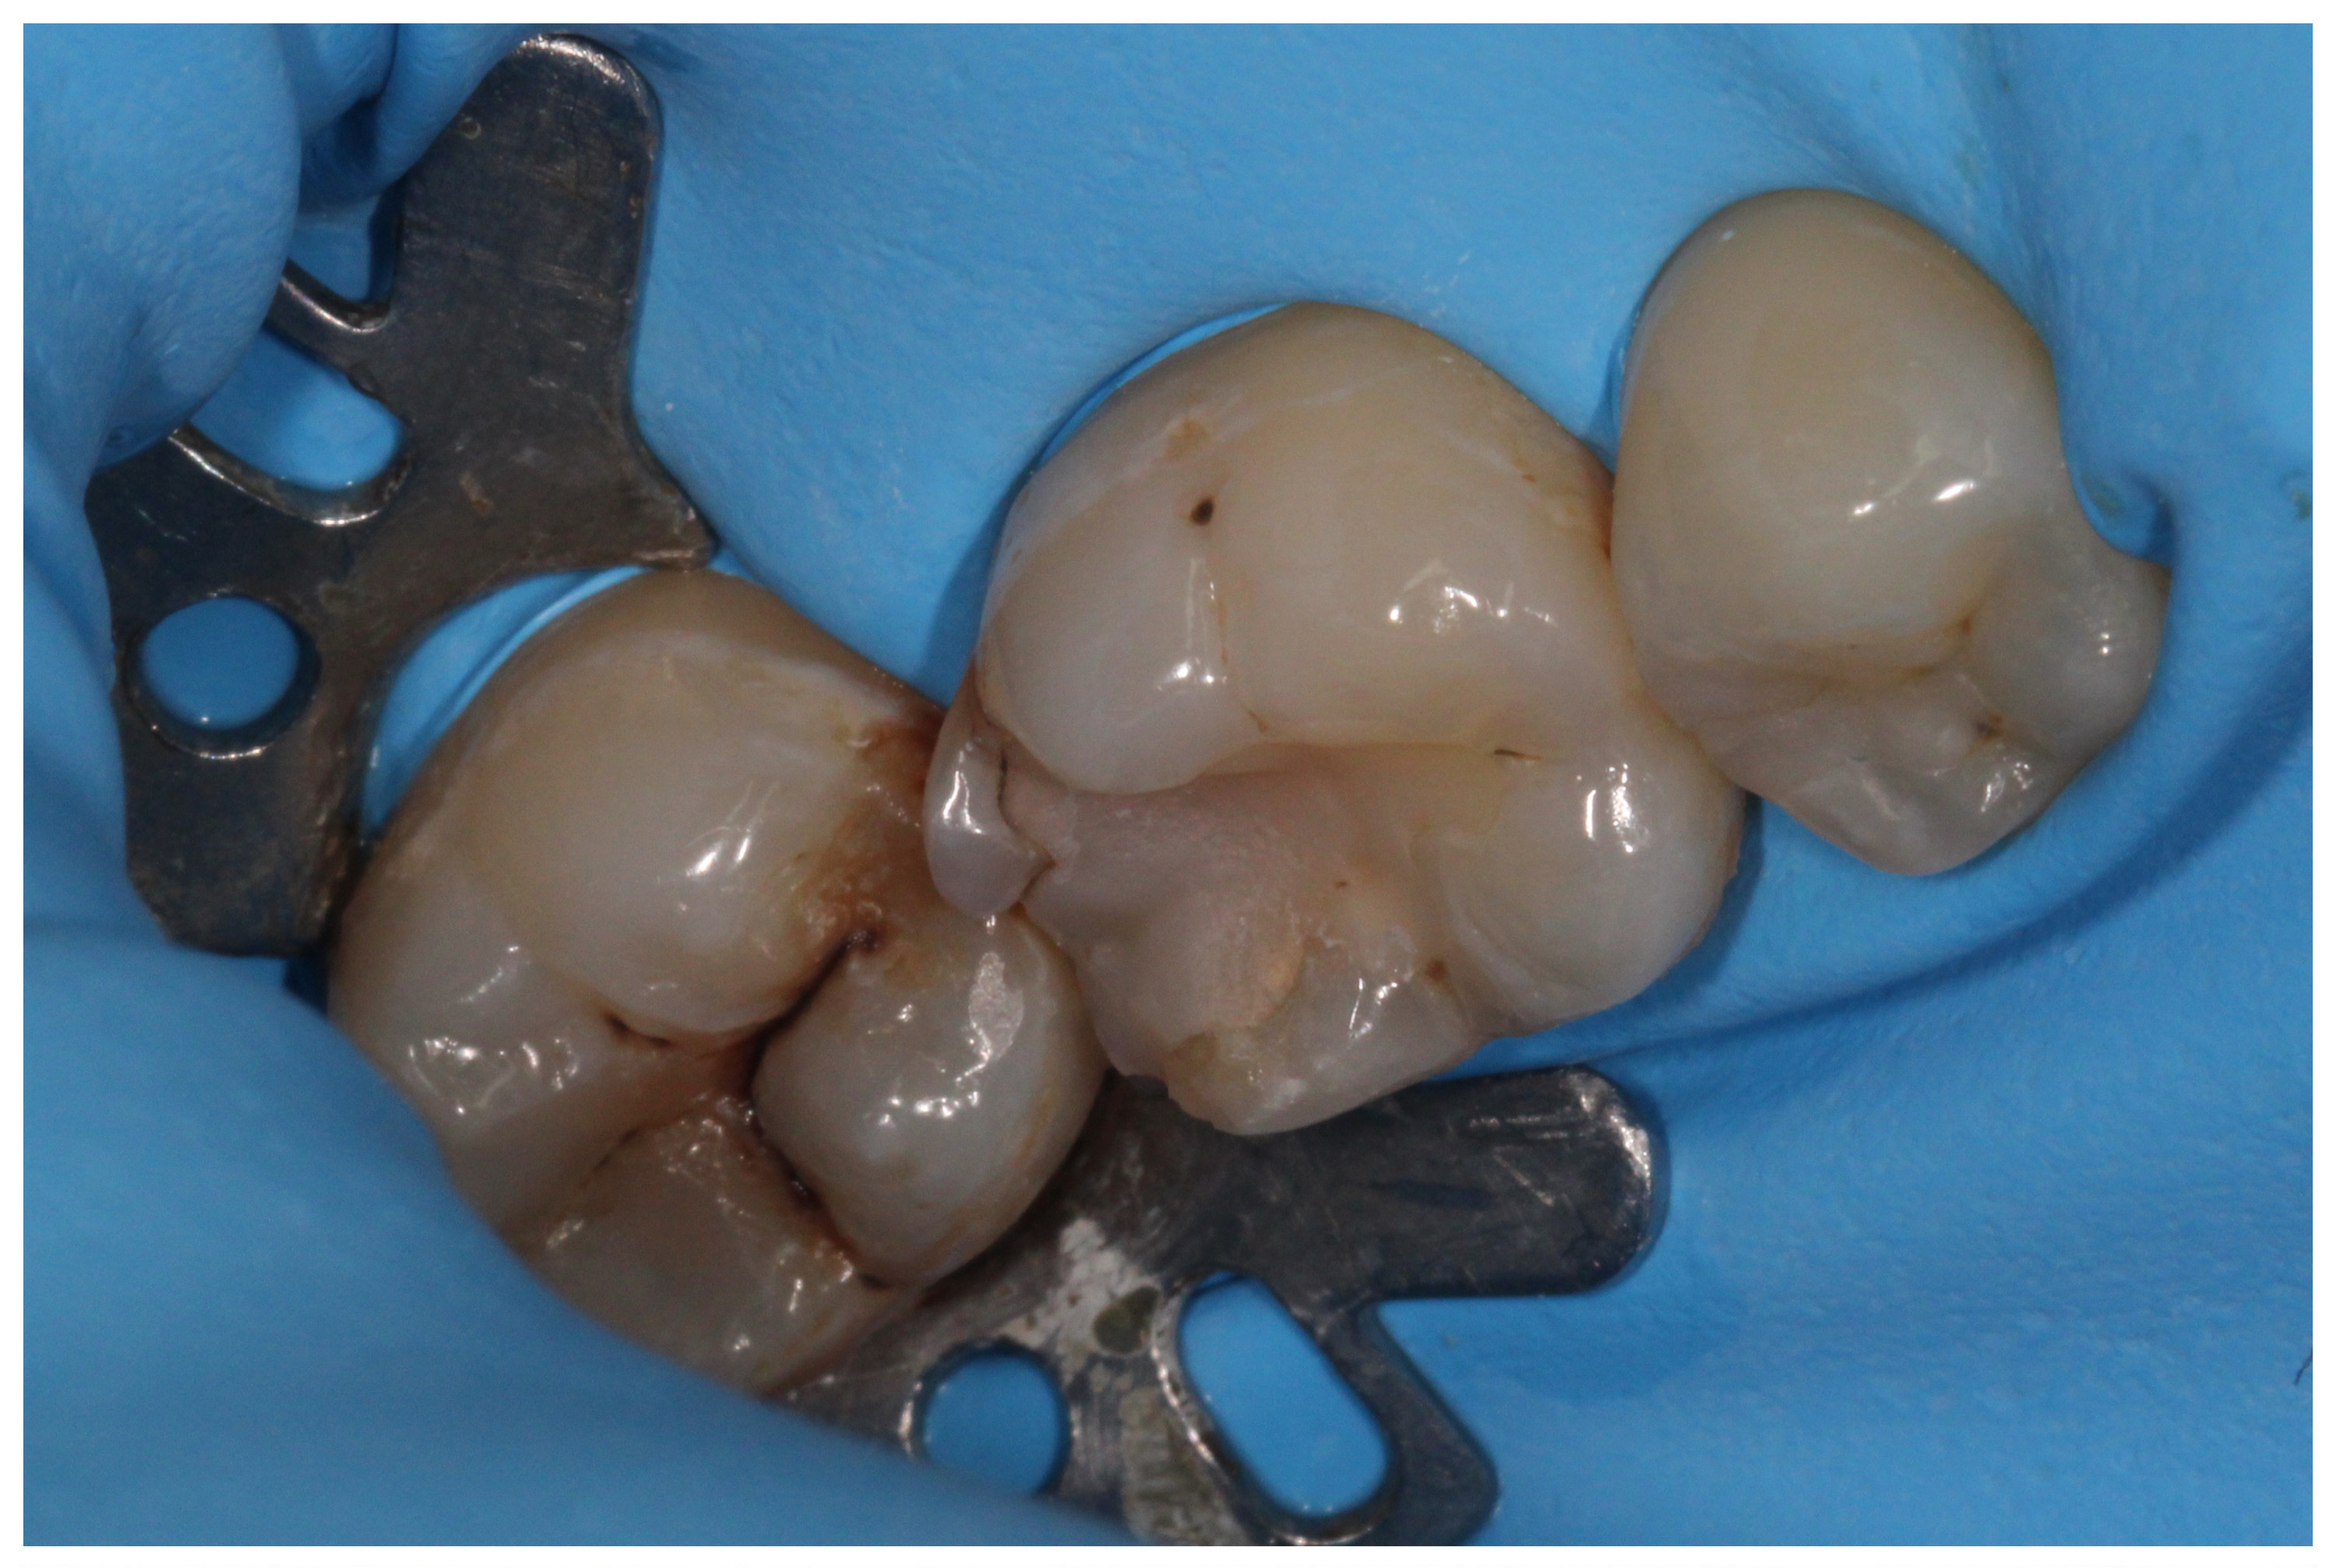

„White“ filling with caries on the first molar, new caries on the second molar

New photocomposite fillings